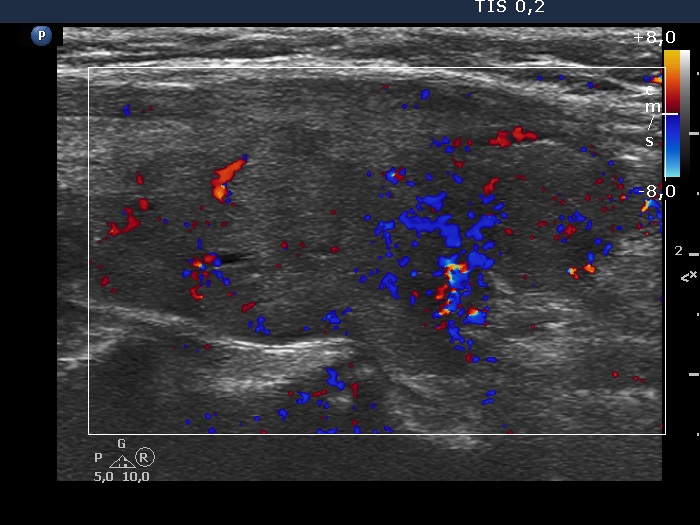

Right lobe, longitudinal scan

Right lobe, longitudinal view, color Doppler mode. The vascularization is not specific.